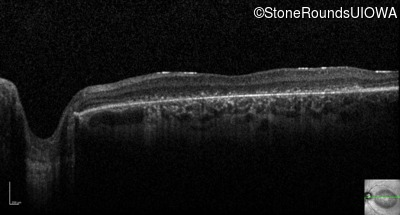

Optical Coherence Tomography - Right - 10/200

Exemplar / OCT Stack